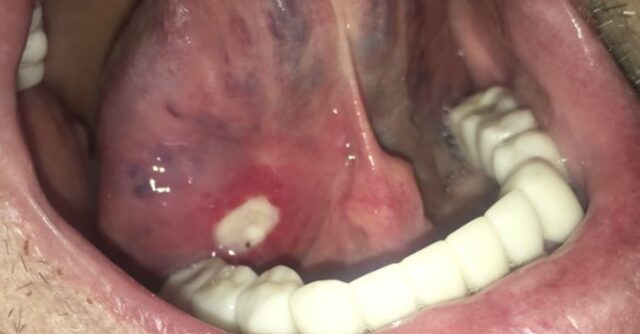

혓바닥밑 통증 혀 밑 돌기 부종 궤양 염증 등으로 인해 아플때